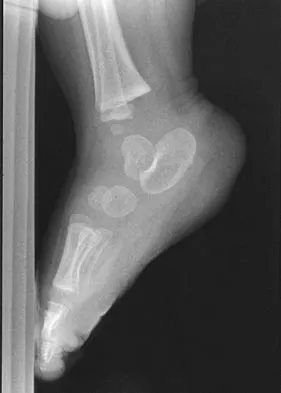

An obese 62-year-old man reports a 10-year history of progressive flatfoot deformity and a 3-month history of a painful callus along the plantar medial midfoot that has not improved with custom shoe wear, pedorthics, and callus care. There is no hindfoot motion, but functional ankle motion remains. He does not have diabetes mellitus. Radiographs are shown in Figures 27a and 27b. What is the best surgical option at this point?

Explanation

The deformity is long-standing, the hindfoot is immobile, and the radiographs reveal severe degenerative arthritis involving the entire hindfoot, severe deformity, and talonavicular dislocation. The "exostosis" responsible for the callus is the talar head; resection would severely destabilize the foot. Degenerative arthritis and fixed deformity preclude lateral column lengthening, medial slide calcaneal osteotomy, and talonavicular arthrodesis. Triple arthrodesis is the only viable option. Johnson JE, Yu JR: Arthrodesis techniques in the management of Stage II and III acquired adult flatfoot deformity. Instr Course Lect 2006;55:531-542.